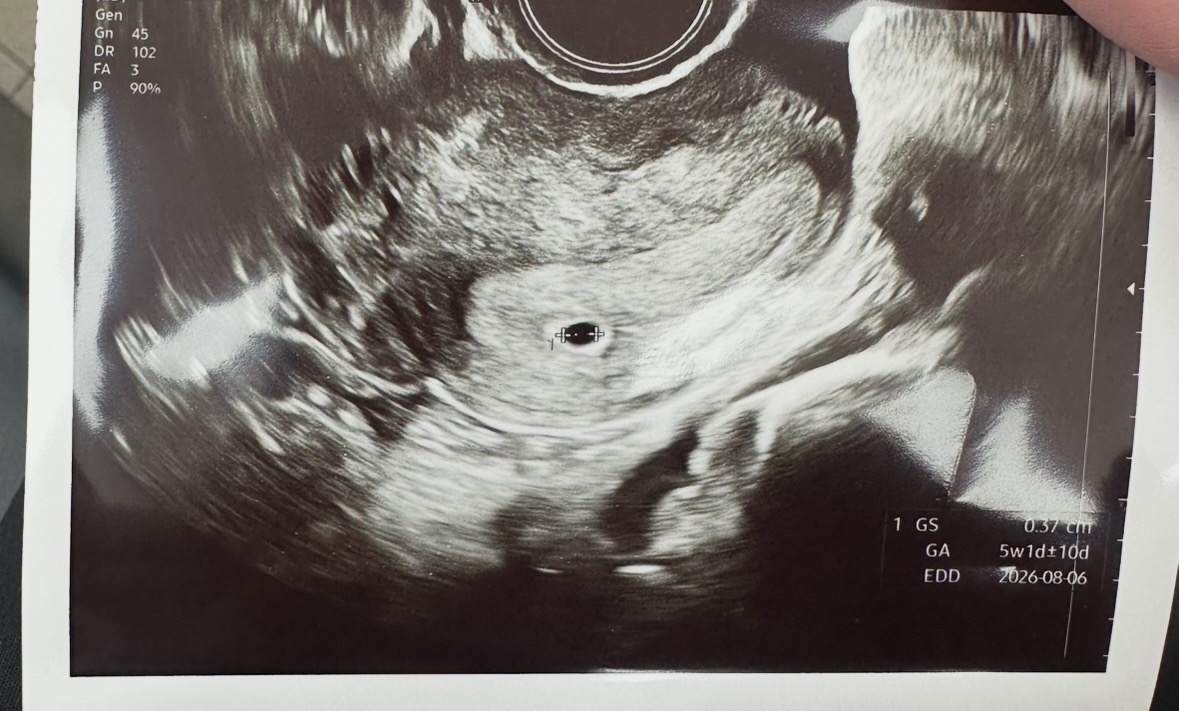

5주차 아기집 확인

아기집 확인하고 왔는데 아기집 괜찮은 상태 맞을까요?ㅠ

자임이시면 착상이 늦게될 수도 있대요~ 저도 생리기준 5주0일에 4mm 아기집 봤는데 크기로는 4주1일이었어요! 아기집 크기로 주수 다시 세주시더라고요~

저 5주에 0.38 이틀뒤 0.71 난황까지봤어요^^

저 딱 5주에 보러가니 4주6일 또는 5주 크기라고 하셨고 4mm 였어요 🤣

저도 5주1일차 추정에 보러갓더니 4주후에서 5주초 정도 4mm로 정상이라고 하셨습니당